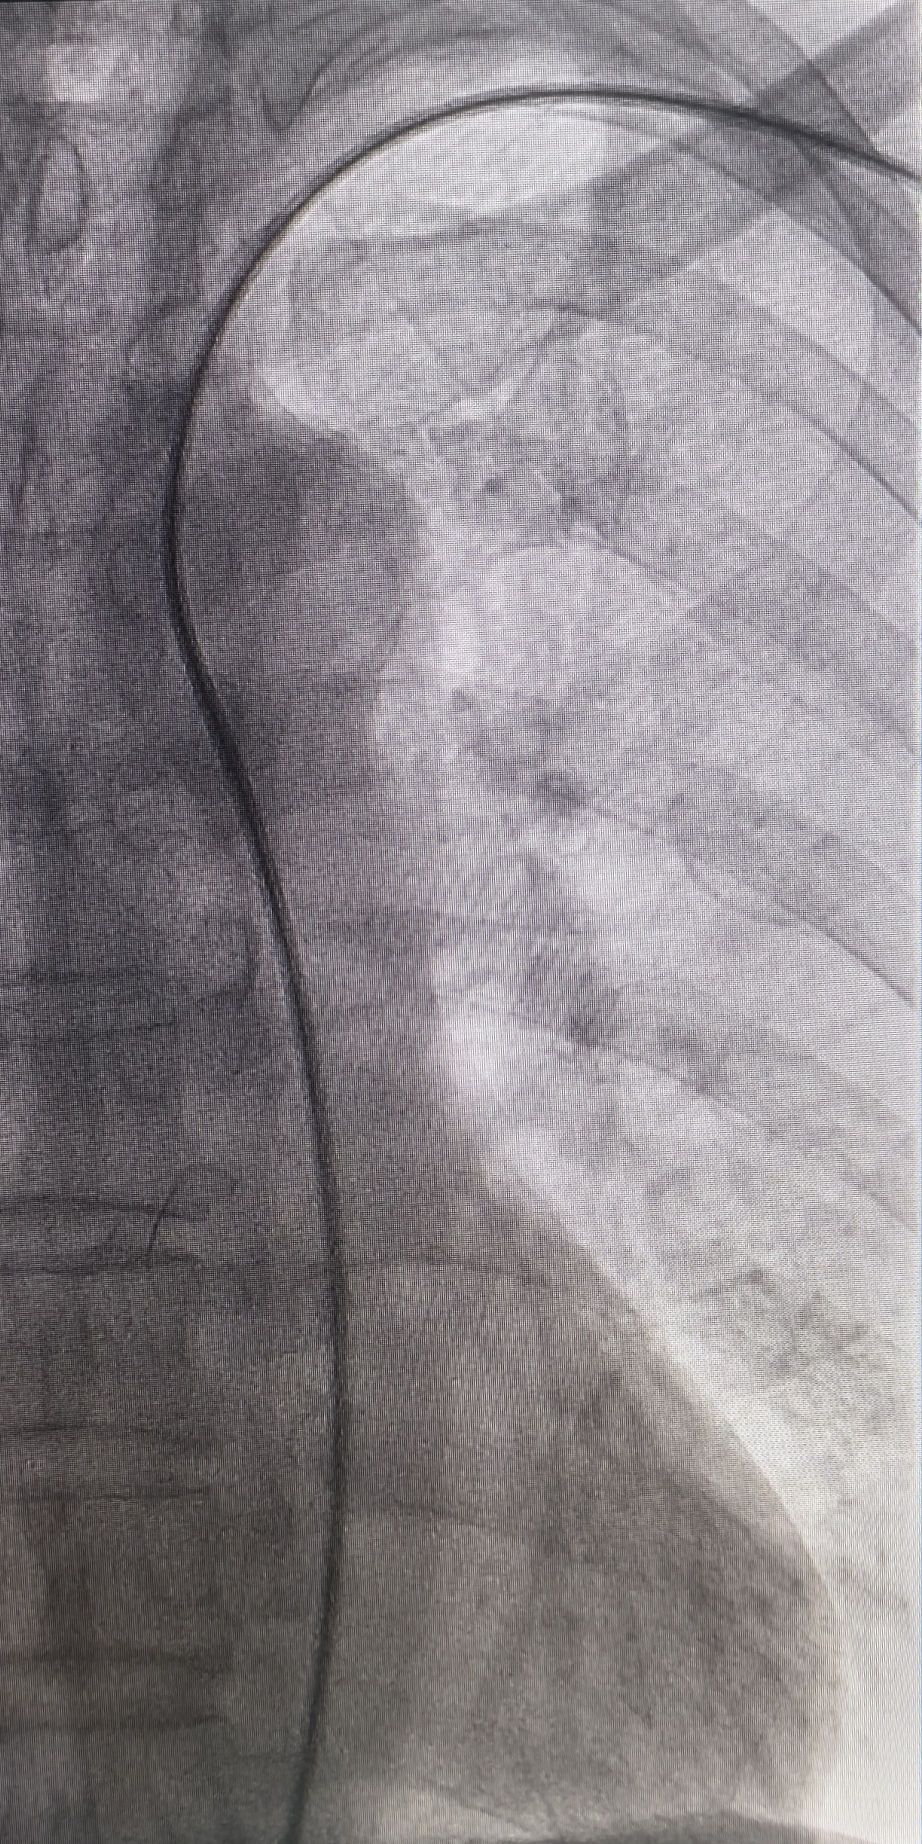

3.沿导丝进入支架(8-80)精准释放于左髂动脉并完整覆盖病变,沿导丝进入球囊行支架内后扩张。复查造影见左髂动脉血流恢复,支架形态可,无明显残余狭窄或造影剂外溢。

动脉长鞘怎么置入桡胜一筹丨吴巍巍主任、赵俊来教授团队:应用Brite Tip RADIANZ长鞘经桡动脉治疗下肢动脉粥样硬化闭塞症一例_https://www.jmylbn.com_新闻资讯_第20张

支架释放

动脉长鞘怎么置入桡胜一筹丨吴巍巍主任、赵俊来教授团队:应用Brite Tip RADIANZ长鞘经桡动脉治疗下肢动脉粥样硬化闭塞症一例_https://www.jmylbn.com_新闻资讯_第21张

术后造影

4.撤出BRITE TIP RADIANZ 经桡导引长鞘顺利,造影可见桡动脉血流通畅,未见动脉痉挛等、血管损伤等。压迫器压迫左桡动脉穿刺点,局部加压包扎。